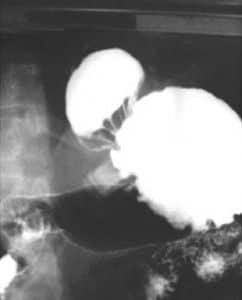

HERNIAS

• DE HIATO

•  DE HIATO-ESTRECHEZ DEL ESTOMAGO